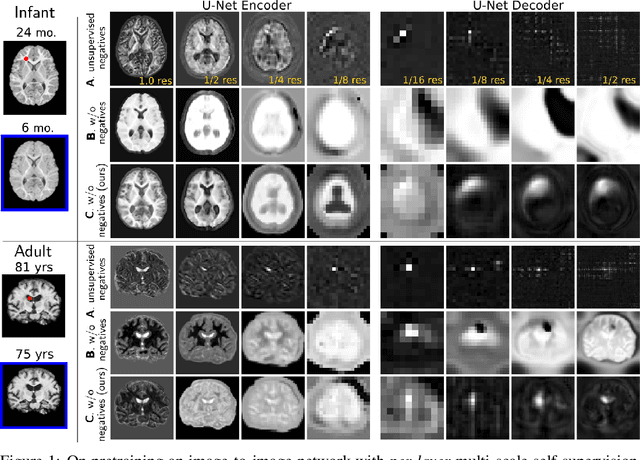

Recent self-supervised advances in medical computer vision exploit global and local anatomical self-similarity for pretraining prior to downstream tasks such as segmentation. However, current methods assume i.i.d. image acquisition, which is invalid in clinical study designs where follow-up longitudinal scans track subject-specific temporal changes. Further, existing self-supervised methods for medically-relevant image-to-image architectures exploit only spatial or temporal self-similarity and only do so via a loss applied at a single image-scale, with naive multi-scale spatiotemporal extensions collapsing to degenerate solutions. To these ends, this paper makes two contributions: (1) It presents a local and multi-scale spatiotemporal representation learning method for image-to-image architectures trained on longitudinal images. It exploits the spatiotemporal self-similarity of learned multi-scale intra-subject features for pretraining and develops several feature-wise regularizations that avoid collapsed identity representations; (2) During finetuning, it proposes a surprisingly simple self-supervised segmentation consistency regularization to exploit intra-subject correlation. Benchmarked in the one-shot segmentation setting, the proposed framework outperforms both well-tuned randomly-initialized baselines and current self-supervised techniques designed for both i.i.d. and longitudinal datasets. These improvements are demonstrated across both longitudinal neurodegenerative adult MRI and developing infant brain MRI and yield both higher performance and longitudinal consistency.